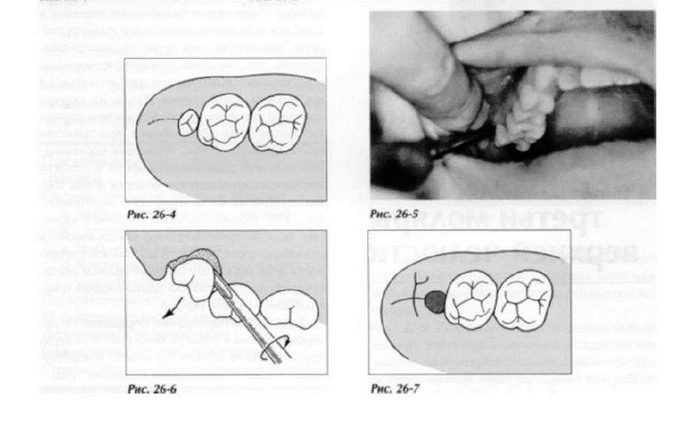

Верхние удаляются схожим образом

Попроще

Если это почти подвижный зуб, корни срослись или расположены параллельно, то можно попробовать достать его щипцами. Для зубов мудрости они специальные

накладываем щипцы и аккуратно расшатываем зуб. Торопиться не надо, дабы не обломать корни и не возиться с их вытаскиванием. Иногда можем помочь себе элеватором. По поводу костной ткани переживать тут особо не надо, имплантатами эти зубы всё равно не замещают. Если что-то выломали, то подшили и заживет.

Если у нас корни растопыренные в разные сторону или вышеуказанный способ не помогает, то как в главе 30, просто распиливаем корни, либо подпиливаем сбоку.